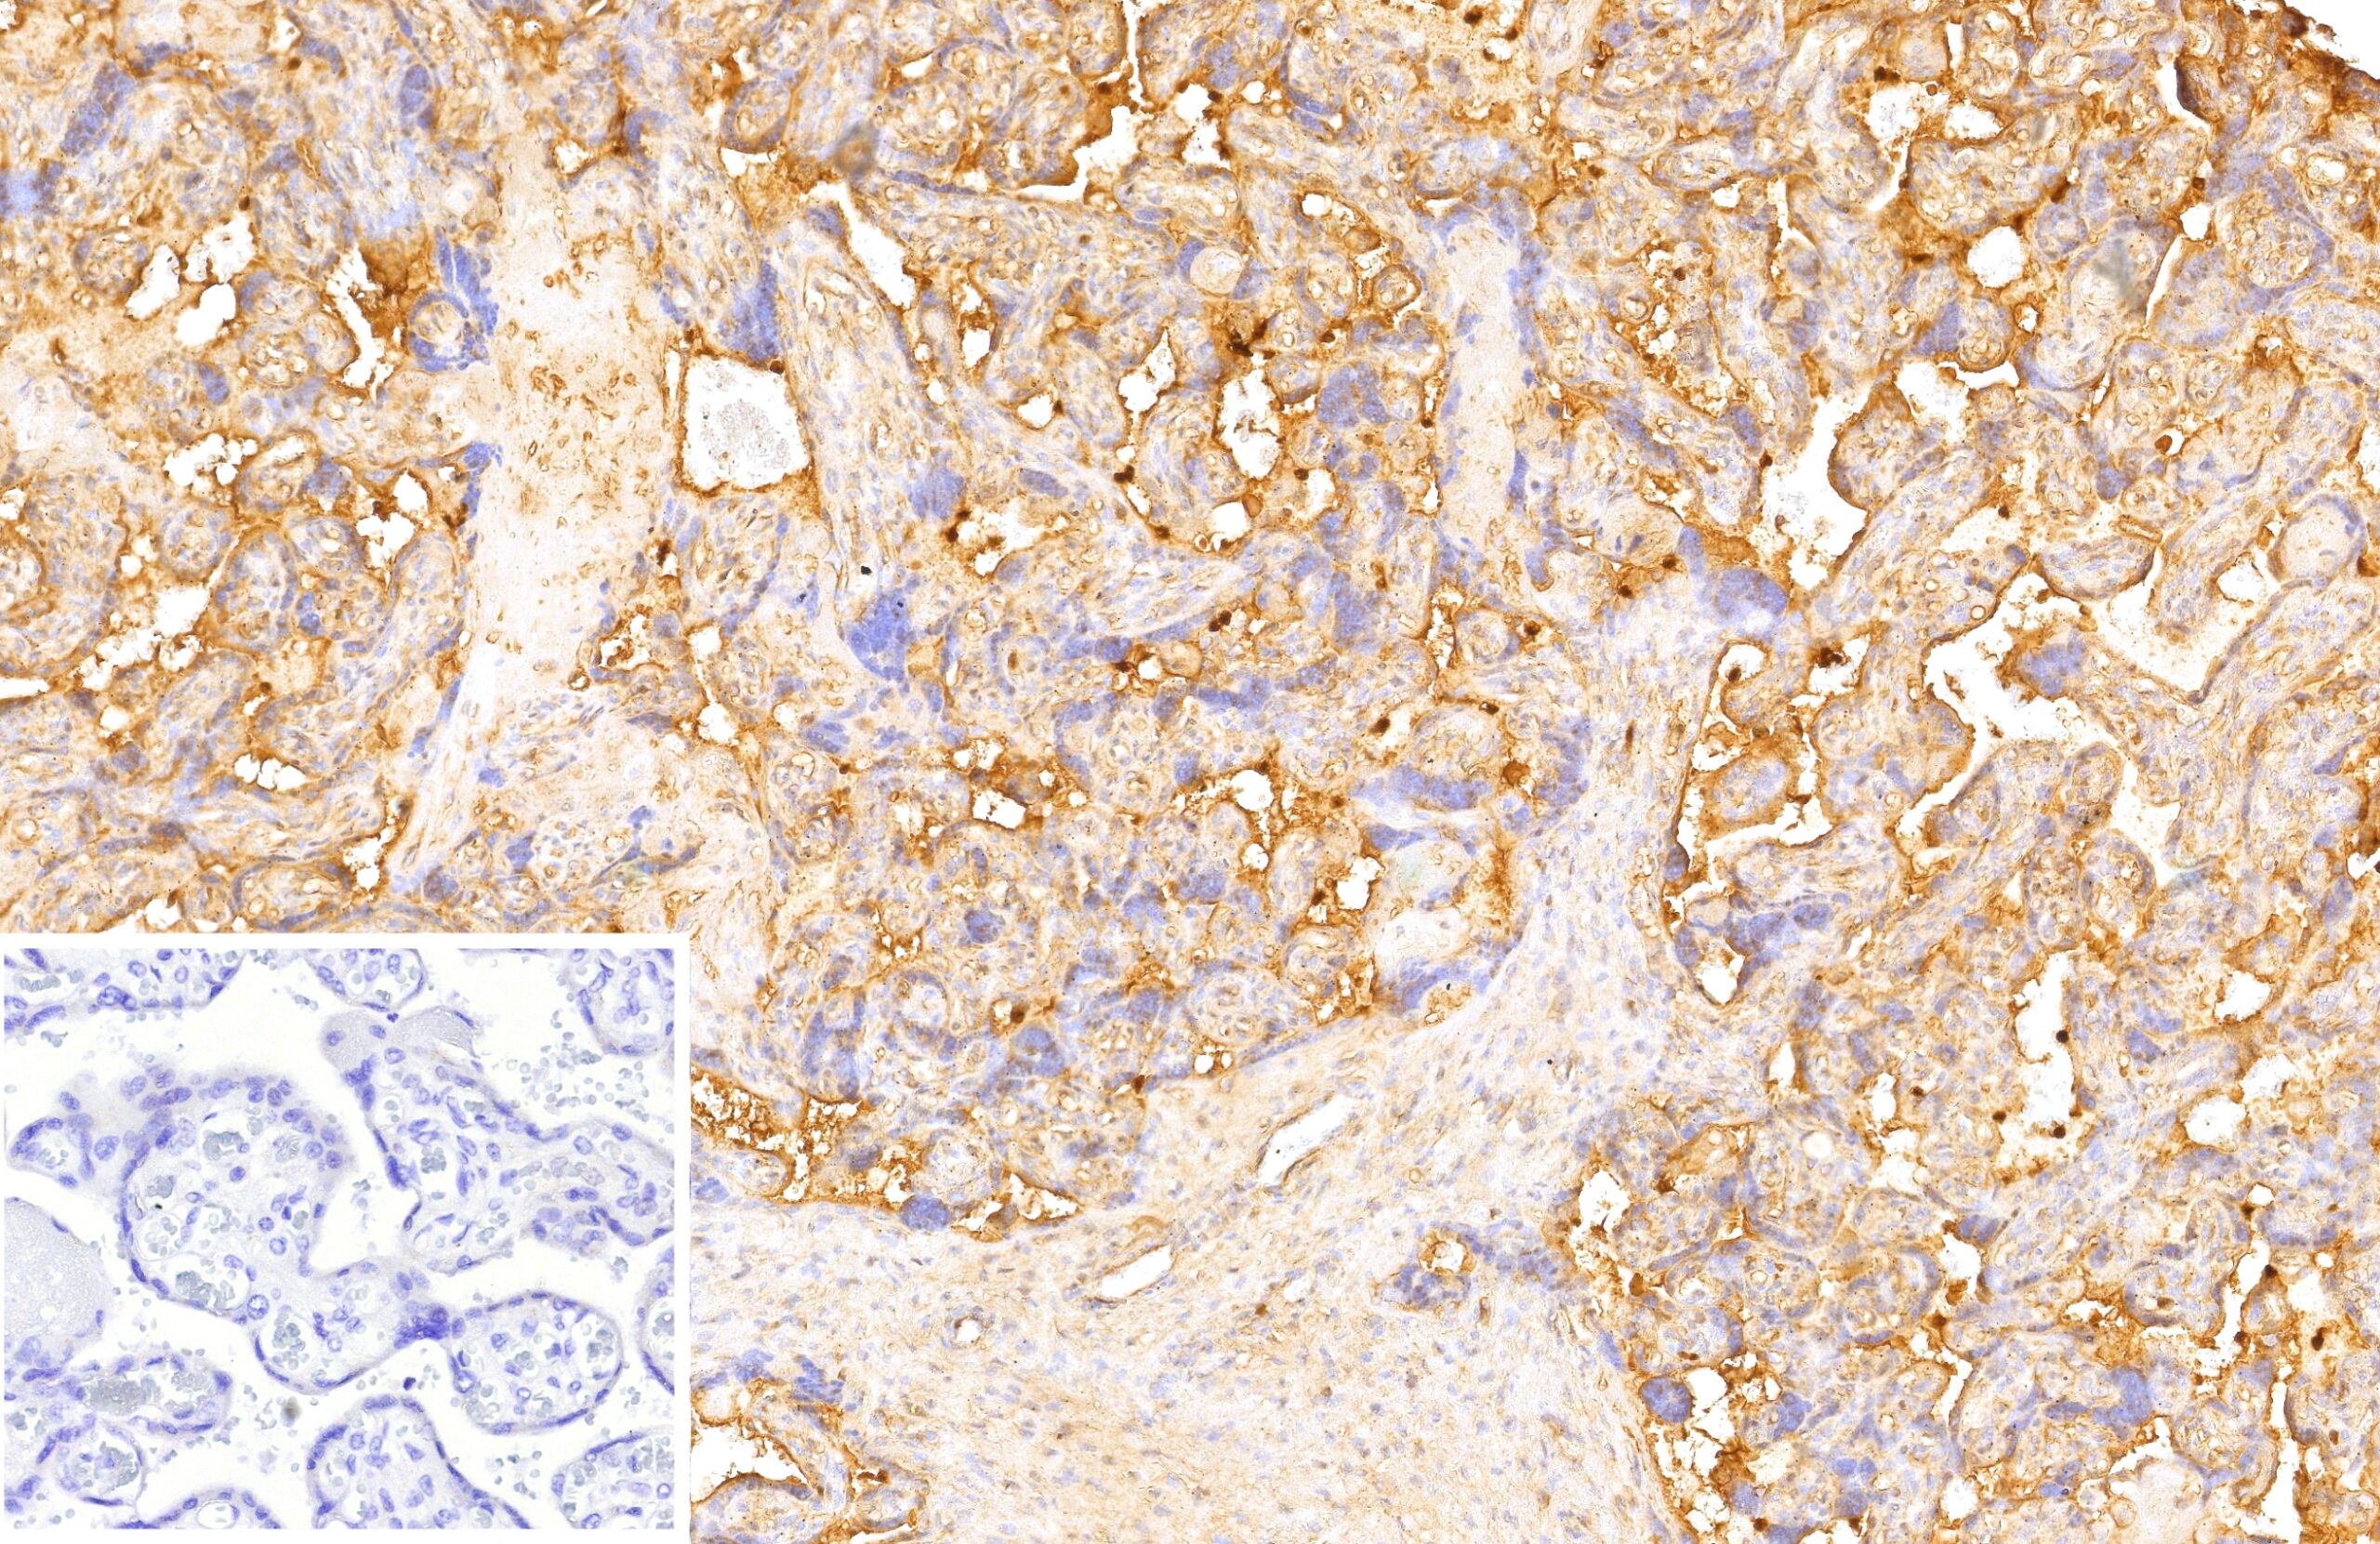

Formalin-fixed, paraffin-embedded human testis stained with VEGI Mouse Monoclonal Antibody (VEGI/13117). Inset: PBS instead of primary antibody; secondary only negative control.

VEGI is an anti-angiogenic cytokine that belongs to tumor necrosis factor superfamily, member 15 (TNFSF15). This protein is abundantly expressed in endothelial cells, but is not expressed in either B or T cells. The expression of this protein is inducible by TNF and IL-1 alpha. This cytokine is a ligand for receptor TNFRSF25 and decoy receptor TNFRSF21/DR6. It can activate NF-kappaB and MAP kinases, and acts as an autocrine factor to induce apoptosis in endothelial cells. This cytokine is also found to inhibit endothelial cell proliferation, and thus may function as an angiogenesis inhibitor. Reduced expression of VEGI has been reported as a marker of poor prognosis in breast cancer.